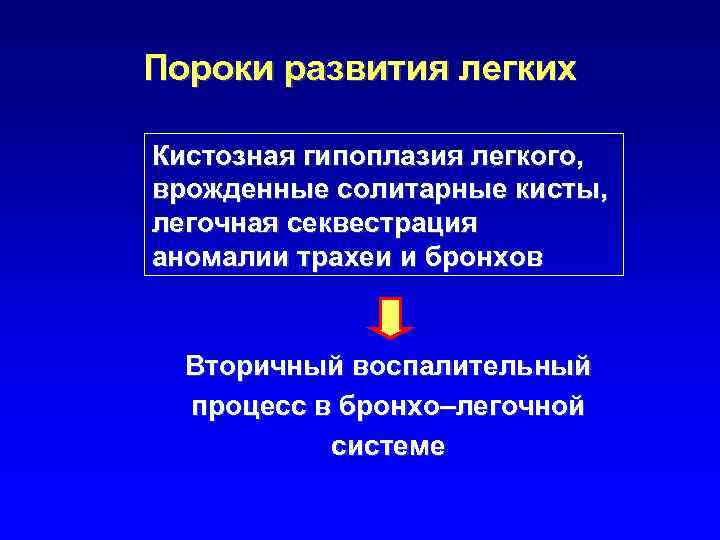

Пороки развития легких Кистозная гипоплазия легкого, врожденные солитарные кисты, легочная секвестрация аномалии трахеи и бронхов Вторичный воспалительный процесс в бронхо–легочной системе